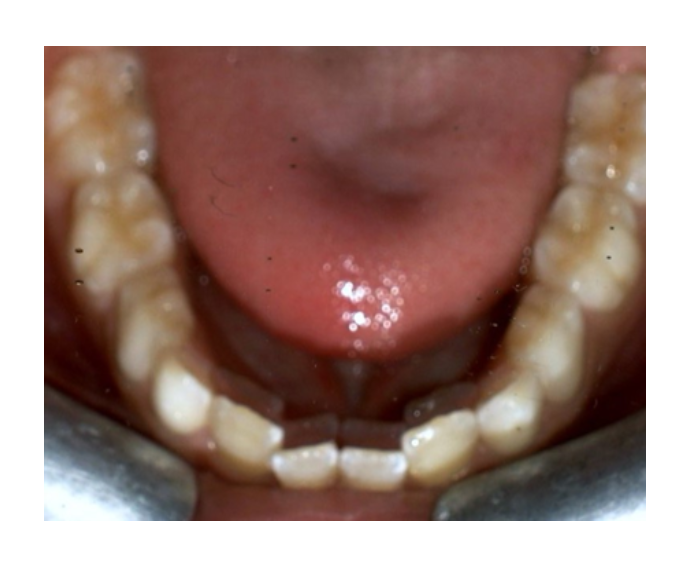

Odontología

infantil